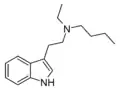

| DET | artificial | H | CH2CH3 | CH2CH3 | N,N-diethyltryptamine | 61-51-8 |